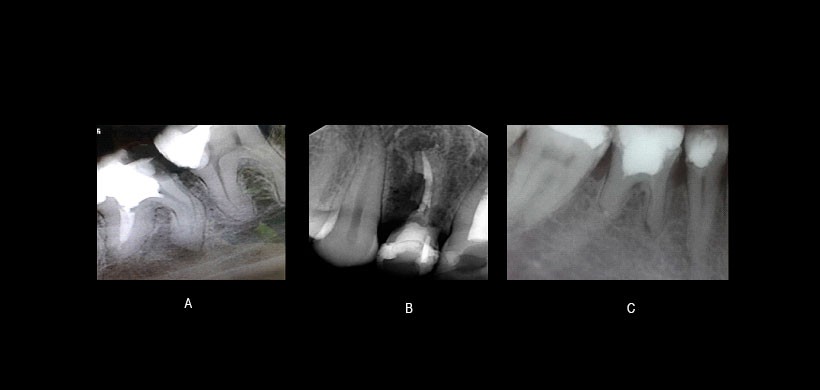

Figura 5: A) Reabsorción radicular externa apical en pieza 47, B) Reabsorción cervical invasiva en la pieza 24 con tratamiento de conducto y sometido a blanqueamiento intraconducto, C) Reabsorción radicular por reemplazo.